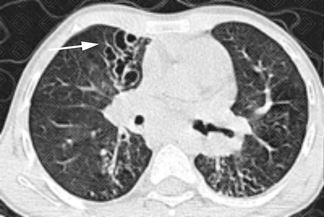

Texto alternativo para a imagem

Texto alternativo para a imagem Créditos: Dra. Elazir Mota - Rio de Janeiro/RJ

Descrição das imagens: Paciente infantil, sexo feminino, 8 anos, com história de aspiração de corpo estranho (milho de pipoca) diagnosticado tardiamente. Tomografia de tórax revela substituição de todo parênquima pulmonar esquerdo sendo ocupado por extensas bronquiectasias, de caráter sequelar. Observa-se na reconstrução tridimensional (3D) a importante destruição do parênquima pulmonar à esquerda (seta branca).